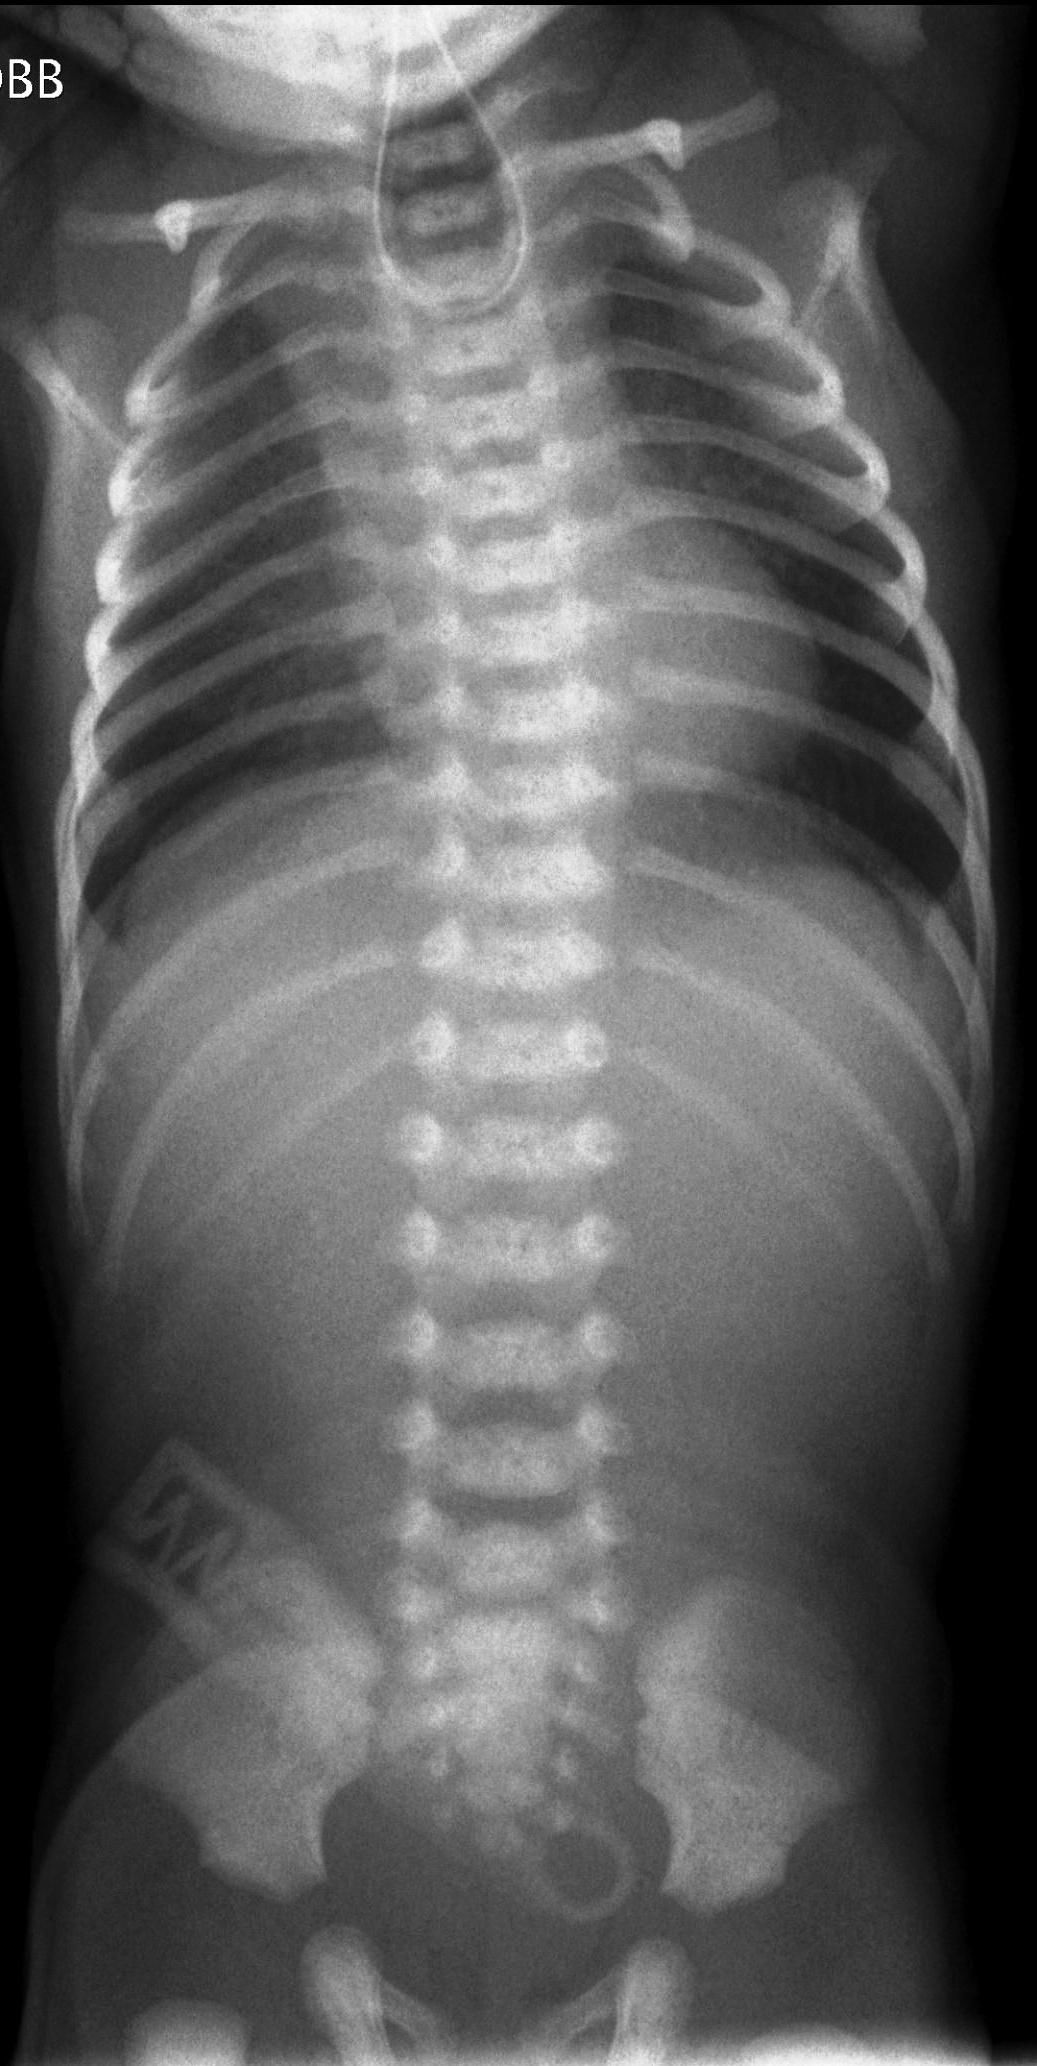

IRDS (Idiopathic respiratory distress syndrome). Preterm infants, younger than 34 weeks, have immature lungs with surfactant shortage that leads to alveolar insufficiency. The breathing disorder progresses with time as tachypnea, dyspnea, cyanosis and grunting occur. On X-ray images the respiratory volume will regress and a diffuse reticular-nodular pattern can be observed, also wide air-bronchograms will appear running to the peripheries. The contours of the heart will be blurred or even a complete loss of transparency is visible (stages I-IV). Surfactant administered in time will result in improved radiologic picture.

3.“White” lung. IRDS.IV.